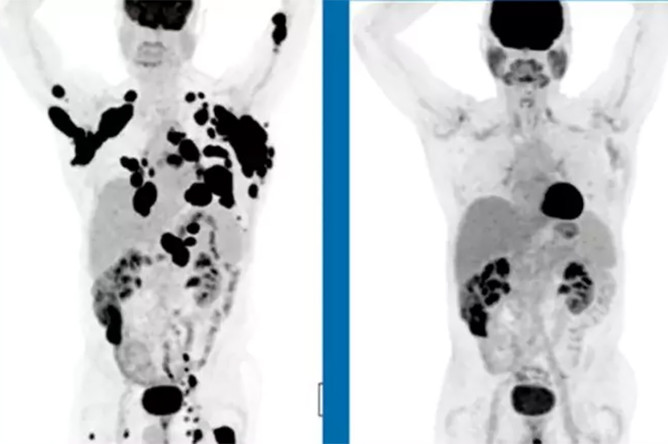

Химеры спасут от тяжелой лимфомы

В США найдено эффективное средство от неходжкинской лимфомы

Лимфома Ходжкина вне списка

Эксперты призывают включить препараты для лечения лимфомы Ходжкина в список ЖНВЛП